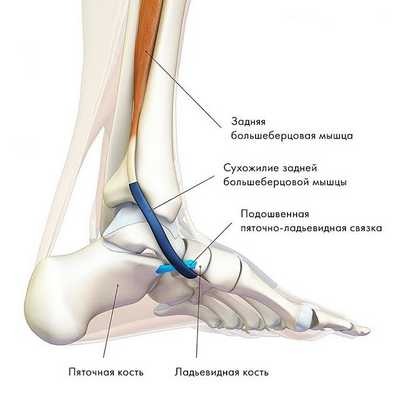

Задняя большеберцовая мышца активна в течение фазы опоры, включается сразу после контакта пятки с опорой и быстро прекращает сокращаться после поднятия пятки. Ее брюшко начинается глубоко внутри задней части нижней конечности, сухожилие следует вниз до задней части медиальной лодыжки, где находится кпереди от сухожилия длинного сгибателя пальцев, заднего большеберцового нейрососудистого пучка (задняя б/б артерия, вена и нерв) и сухожилия сгибателя большого пальца. Все эти структуры ограничиваются удерживателем сгибателей возле медиальной лодыжки. Сухожилие задней б/б мышцы проходит в борозде позади и ниже медиальной лодыжки, разделяясь на 3 части у медиальной стороны тарана. Передняя часть прикрепляется к бугристости ладьевидной кости, средняя часть продолжается в плантарную тарзальную область и прикрепляется к плантарной части клиновидных костей, кубовидной и в основании 2, 3 и 4 метатарзальных костей. Задняя часть внедряется как пучок в переднюю часть нижней пяточно-ладьевидной связки. Медиальная лодыжка работает как многороликовый блок, позволяя сухожилию задней б/б мышцы изменять направление тяги, и эти точки прикрепления обеспечивают супинацию заднего и среднего отделов стопы во время переноса веса, в то время как происходит стабилизация арочной конструкции среднего отдела.

2. Заднее большеберцовое мышечное образование, берущее начало в районе малоберцовой и большеберцовой костей и, с другой стороны, прикрепленное к ладьевидной кости, отвечает за инверсию стопы, ее сгибание в голеностопе и (ключевая функция) стабилизацию ее свода.

Сухожилие задней большеберцовой мышцы — одно из важнейших сухожилий нижней конечности. Сухожилие — это анатомическое образование, посредством которого мышца прикрепляется к кости. Сухожилие задней большеберцовой мышцы располагается в области внутреннего края стопы. Основной функцией этого сухожилия является поддержание свода стопы и стабилизация стопы при ходьбе.

Сухожилие задней большеберцовой мышцы располагается вдоль внутренней поверхности голеностопного сустава и стопы.